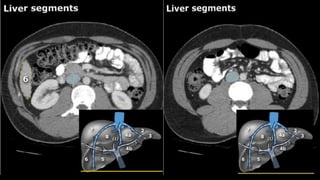

•Liver • A normalliver enhances homogeneously (irrespective of the scan phase). The liver receives about 80% of its blood through the portal vein (= nutrient-rich blood from the intestines). The remaining 20% is supplied by the hepatic artery. y is present, it is important to document its location. This may be crucial to any surgical options. Using the Couinaud classification, the liver is subdivided into eight individually functioning segments. Each segment has its own afferent hepatic artery and portal vein, and efferent hepatic vein and efferent bile ducts

Liver segments Radiopaedia.com1

• 5.

• 6.

• 7.

• 10.